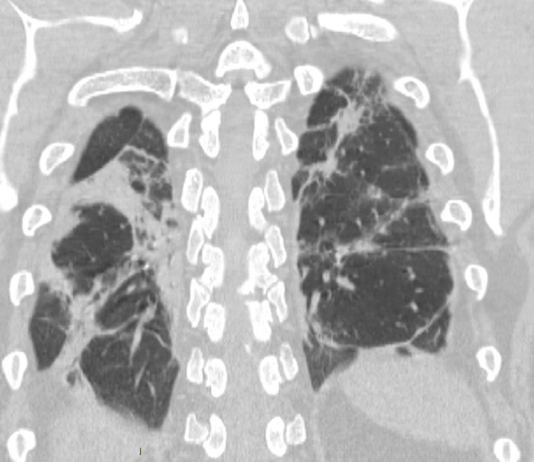

Maschio, 39 anni. Anamnesi patologica remota muta.

Giancarlo GISMONDO VELARDI, Letterio MILITANO, Giuseppe E. GRECO, Ilaria V. TRECROCI, Matilde LICO, Giuseppe CASUSCELLI, Antonino BOVA, Vincenzo FIORILLO, Sandro BALDARI

Dipartimento dei Servizi Sanitari - U.O. Radiologia – ASP Vibo ValentiaMaschio, 47 anni. Anamnesi patologica remota muta.